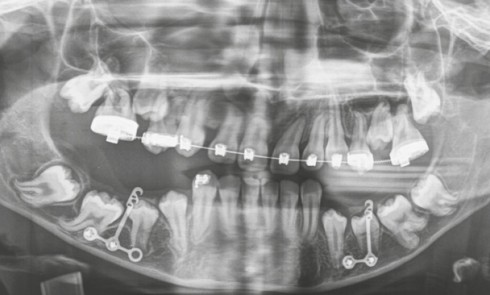

Article réservé à nos abonnés Discussion autour d’un cas complexe d’inclusions multiples atypiques

En l’absence d’obstacle mécanique et d’antécédents médico-chirurgicaux particuliers, le cas décrit précédemment évoque un tableau clinico-radiologique de défaut primaire d’éruption...